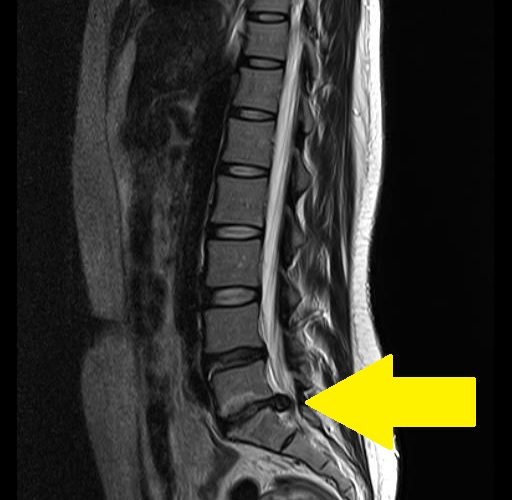

人間の背骨は24個の椎骨が積み重ねってできており、椎骨と椎骨の間にあるクッションのようなものがあります。このクッションのような役割をしている円盤状の軟骨が「椎間板」です。椎間板が出てきてしまい、神経を圧迫して痛みや痺れを感じる病気が「椎間板ヘルニア」と呼ばれます

ちなみに「ヘルニア」とは身体の中の一部(臓器など)が本来あるべき場所から出てきてしまう状態を指すものです。そのため「椎間板ヘルニア」は「椎間板が本来あるべき場所から出てきた状態」となります。ヘルニアが起こる場所は椎間板だけではありません。例えばおへそが飛び出ている「でべそ」もヘルニアの仲間です。正式には「臍ヘルニア」と言います。

背骨は肩の方から腰に向かって負荷がかかりやすいので、ヘルニアになりやすいのも腰の辺りが一番多いと言われています。その結果腰の辺りに痛みを感じる「腰椎椎間板ヘルニア」になる方が多いです。お尻から太ももの裏側のしびれ(坐骨神経痛)が症状としてでてくるのも、腰椎椎間板ヘルニアの特徴です。50歳代以降の方の発症がよく見られます。